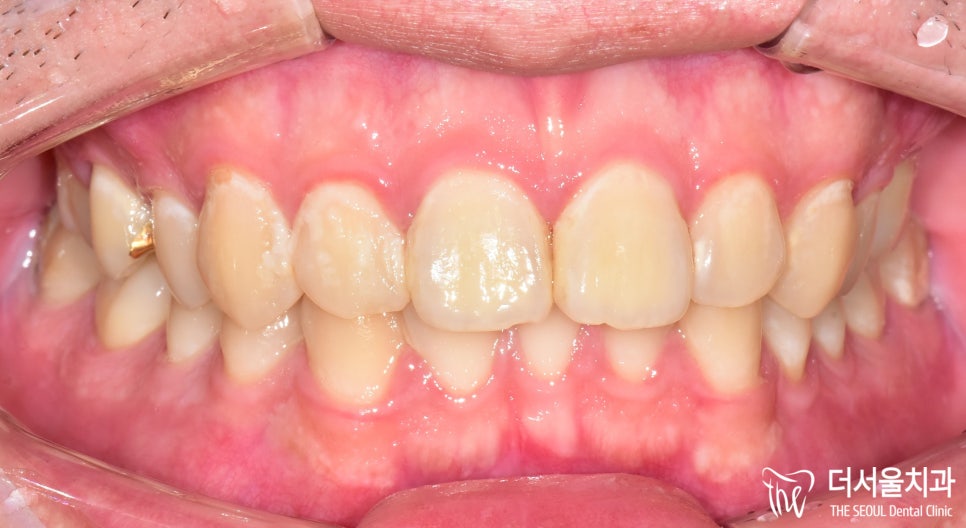

정면을 보면 그렇게 큰 문제는 있는 것처럼 보입니다.

그런데 문제는 정면이 아닌 옆이었는데요.

왼쪽에 작은 어금니 하나가 비었죠?

25번 어금니를 상실해 있습니다.

교합면을보면 뭔가 좁다는 느낌을 받을 수 있는데,

치아를 상실한지 조금 오래 되었다 하셨습니다.